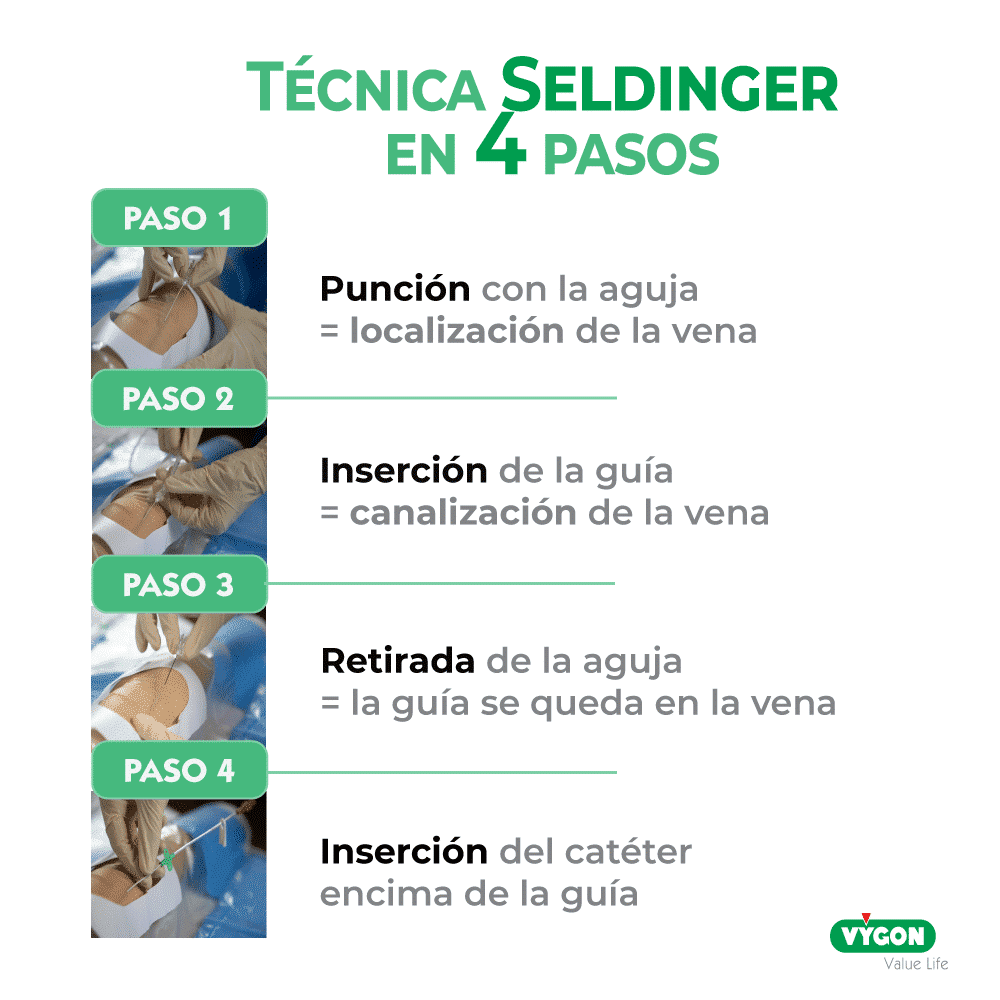

Una línea media se inserta con técnica Seldinger: es conocida en las UCI por ser el método de introducción de las vías centrales y de los catéteres arteriales.

La técnica Seldinger puede ser pura, simplificada o modificada.

La ventaja de cualquiera de las técnicas Seldinger es que la aguja sirve solo para localizar la vena. La guía sirve para canalizar la vena y guiar el catéter. Se trata de la técnica “over the wire” = encima de la guía. Al no tener el catéter junto a la aguja, no se necesita canalizar en el momento de la punción, significa que el gesto se hace en varias etapas y de esta forma es mucho menos invasivo.

• La técnica Seldinger pura es la técnica con dilatación

• La técnica Seldinger simplificada es la técnica sin dilatación

• La técnica Seldinger modificada (o MicroSeldinger) es la técnica con introductor pelable, que lleva en su interior un dilatador que se deja. Entonces se quita la guía y el dilatador interno. De esta forma, el introductor sirve de guía para insertar el catéter.